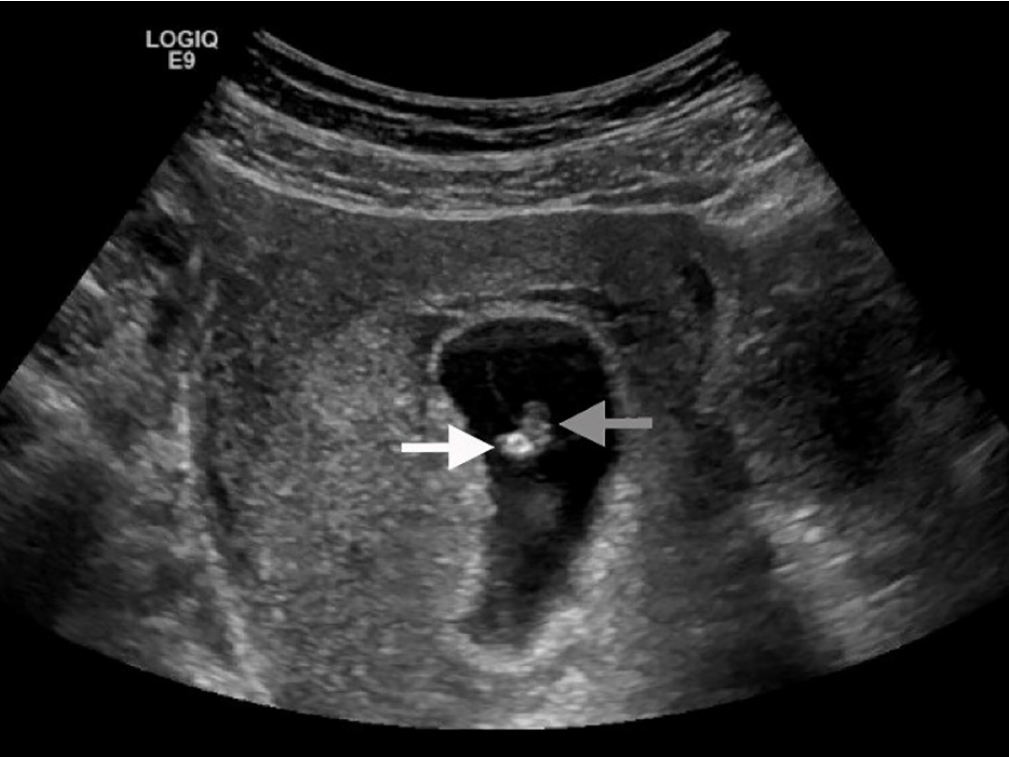

・POCUS:胎芽と隣接する高輝度な卵黄嚢を認めた、胎児心拍は認めず

灰矢印:胎芽、白矢印:高輝度エコーの卵黄嚢

*後方にacoustic shadowを認める